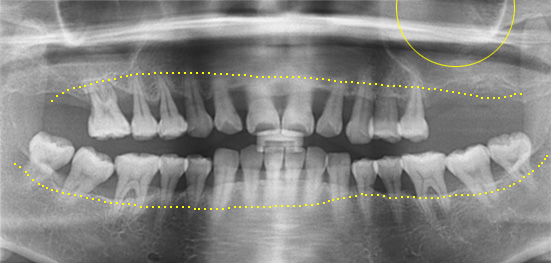

잇몸 뼈가 녹아내려 임플란트 12개 진단을 받고 내원한 환자, 고운미소에서 치주치료를 시행한 결과 전치부 잇몸이 개선되어 발치 하지 않고

크라운으로 수복하였고, 어금니는 상악동거상술 후 6개의 임플란트를 식립하였습니다.

잇몸 염증으로 치조골 손실이 많은 상태

잇몸 건강이 회복된 앞니는 크라운으로 수복